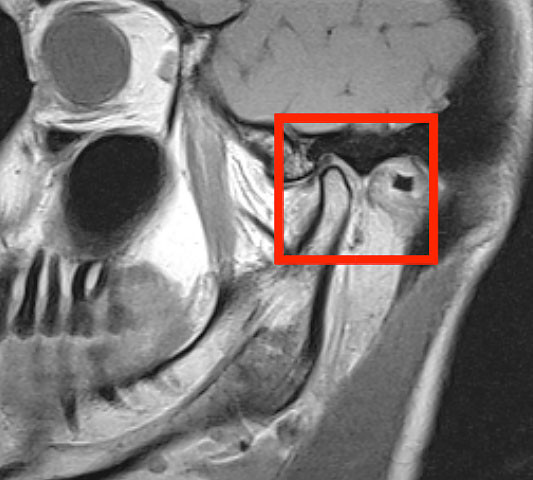

Die Funktionsstörungen des Kiefergelenks stellen eine Herausforderung sowohl an die Patienten als auch an die behandelnden Zahnärzte, Orthopäden, Hals,- Nasen, -Ohren,- Ärzte und die behandelnden Manualtherapeuten dar. Ein Grund dafür sind die vielfältigen anatomischen Zusammenhänge des Kiefergelenks zum gesamten Bewegungsapparat.

Hier spielt die enge Beziehungen zu den Zähnen, der Hals- und Brustwirbelsäule, den oberen Kopfgelenken, den Ohren, zu den angrenzenden Schädelknochen und den nervalen Verbindungen (Hirnnerven) des Kiefergelenks eine wichtige Rolle. Dies macht eine genaue Anamnese und funktionelle Untersuchung und Inspektion des Kiefergelenks, sowie des angrenzenden Bewegungsaparates unumgänglich und zwingend erforderlich. Wünschenswert und sehr wichtig ist dabei die interdisziplinäre Zusammenarbeit zwischen Patient, dem behandelnden Arzt und Therapeuten.